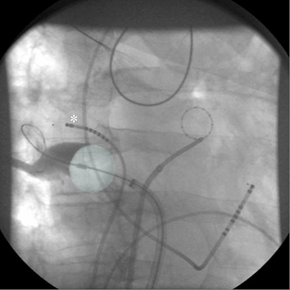

Complete isolation of the pulmonary veins (PV) is considered the cornerstone of catheter intervention to treat atrial fibrillation (AF). PV isolation using a cryoballoon has evolved into a relatively simple alternative for point-by-point radiofrequency current (RFC) ablation because this technology theoretically allows for PV isolation with a single application. The technique has a steep learning curve and can be performed with fluoroscopic guidance without a 3-dimensional mapping system or additional imaging techniques.(1) To achieve continuous lesions, an occlusive balloon position at target PV sites as confirmed by PV angiography is necessary to limit convective heating by leaking blood flow (Figure 1). This may be challenging especially at the right inferior PV due to its proximity to the transseptal puncture site. However, using special catheter maneuvers based on the individual anatomy, complete PV isolation is possible in the great majority of patients (97%) with a single balloon and without additional "touch-up" lesions by a focal cryocatheter.(1) If PV occlusion cannot be achieved, the "pull-down" technique may be used, with freezing initiated at the superior PV circumference, accepting a small inferior leakage. When steady-state balloon temperature is achieved both the sheath and the frozen balloon are pulled down to close the inferior leakage. Successful ablations generally reach a minimal balloon temperature of -40°C or less.(2)

There are currently two available diameters of the Arctic Front™ cryoballoon (Medtronic Cryocath LP), 23 and 28 mm. In our laboratory, we only use the big (28 mm) balloon. The major rationale behind the big cryoballoon strategy is procedural safety by using an intentionally oversized balloon deploying lesions as proximal as possible at the PV antrum. In addition to energy delivery to PV tissue, a deep position inside the vein results in the combined effect of close proximity to adjacent structures and deeper freezing temperatures due to less convective heating of the balloon by atrial blood flow. Accordingly, right-sided phrenic nerve palsy (PNP), the most frequent complication associated with cryoballoon PV isolation, has been reported in a significantly higher rate using the 23mm (12.4%) when compared to the 28mm balloon (3.5%).(3) Although transient in the great majority of patients, PNP may occur due to the close anatomical relationship of the right phrenic nerve to the septal (especially right superior) PVs. In addition to avoiding distal balloon positions, diaphragm movement has to be monitored continuously when freezing at the septal PVs. This is usually performed by high-output pacing of the right phrenic nerve proximal to its intersection with the right superior PV from the superior caval vein (Figure 1, asterisk), and manual palpation of the resultant diaphragm contractions. If weakening of the contractions occurs, cryoablation is immediately stopped. Diaphragmatic electromyography is investigated as a more sensitive tool for the early detection of PNP.(4)Balloon size also plays a role in possible collateral damage to the esophagus. In total, 116 patients have been included in 3 studies with systematic endoscopic screening for esophageal lesions after cryoballoon PV isolation (3). Esophageal ulcerations (6/35, 17%) were only reported in the study using both balloon sizes (and a focal cryocatheter if needed). In the remaining 81 patients from 2 studies employing a single 28mm balloon strategy, no esophageal lesion was found.(3,5) This may be explained by a deviation of the esophageal course from the midline in the great majority of patients, resulting in close proximity of the esophagus to the posteriorly directed inferior PVs. As of today, no atrio-esophageal fistula has been described following cryoballoon ablation, reported esophageal ulcerations healed without clinical sequelae.